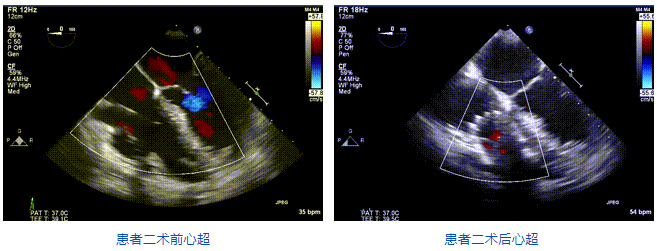

2021年12月24日,復旦大學附屬中山醫院葛均波院士團隊成功應用LuX-Valve Plus為一例極重度三尖瓣反流(TR)合并房顫、房缺的患者完成了經血管三尖瓣置換術,這是在前基礎上,本周完成的第三例經血管三尖瓣置換手術,葛均波院士、周達新教授等與心外科魏來教授、賴顥教授,心超室的潘翠珍教授、李偉教授及麻醉科的郭克芳教授共同完成了本周手術,均獲得圓滿成功!患者術后超聲顯示無TR,臨床癥狀明顯改善。本周手術的成功也為LuX-Valve Plus救治性臨床研究添上了濃墨重彩的一筆。

三例患者入院后,葛均波院士團隊周達新教授、潘文志教授、張源博士、陳莎莎博士及心超室的潘翠珍教授、李偉教授對患者的情況進行詳細評估和討論,最終決定為三例患者選擇LuX-Valve Plus40mm、50mm和50mm型號的瓣膜進行手術治療。手術后即刻拔除氣管插管,術后患者三尖瓣反流癥狀得到顯著改善,復查心超結果顯示人工三尖瓣瓣膜支架固定穩定,瓣葉關閉形態未見異常,未見明顯反流。